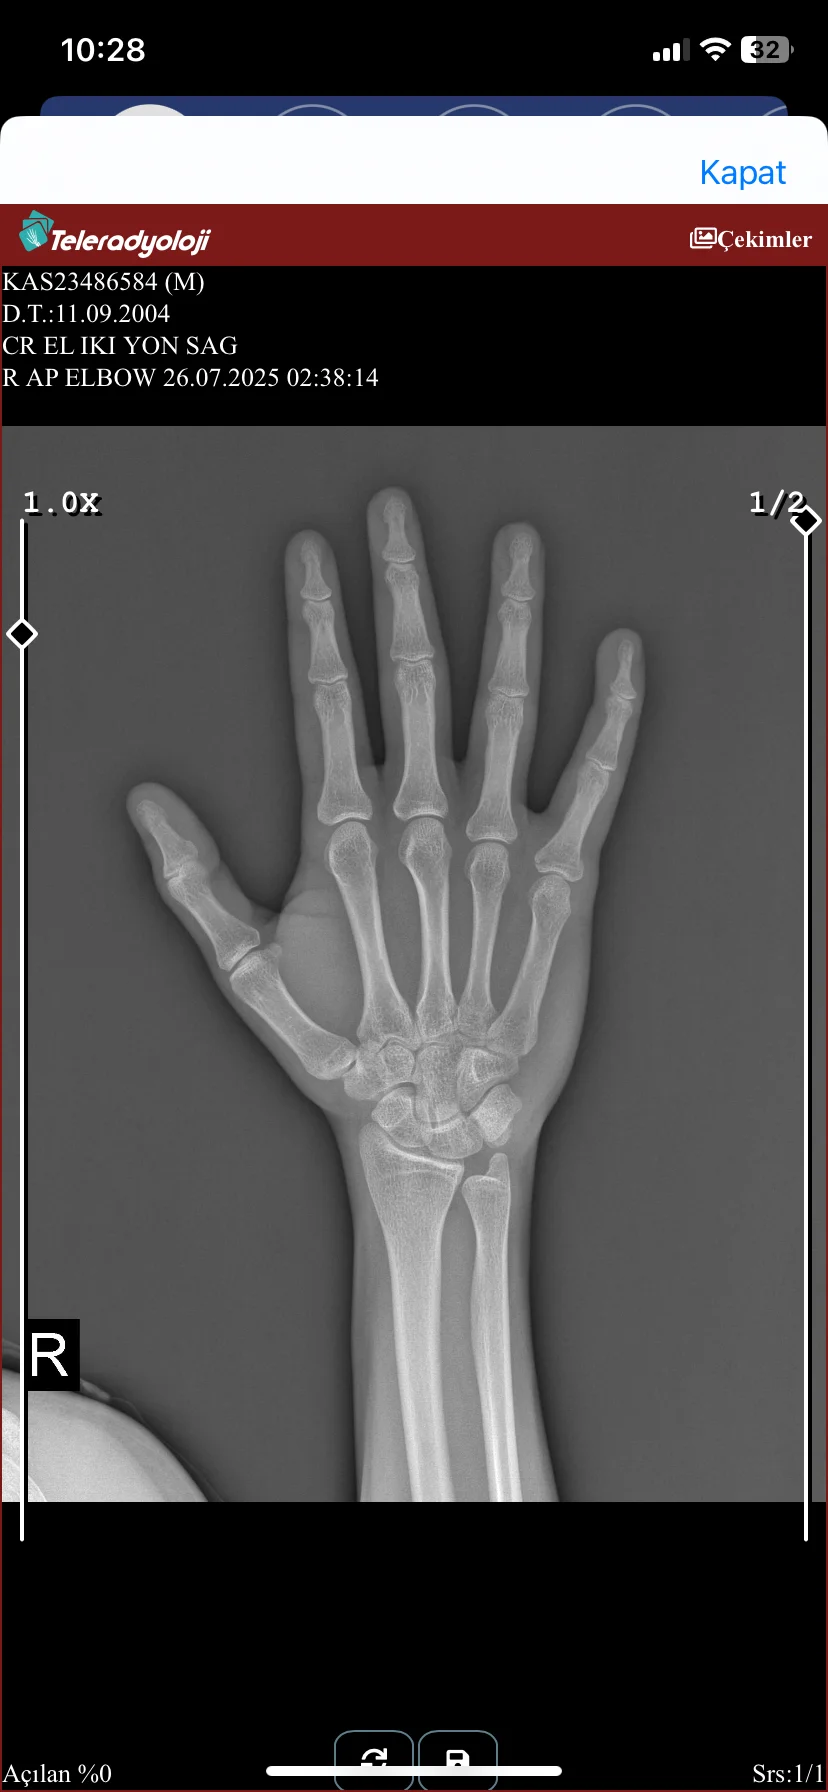

Dün akşam talihsiz bir olay yaşadım vücudumda sorun yokken sağ el serçe parmağım ağrıyıp sızlıyordu şişmişti hastaneye gittim kan aldılar röntgen çektiler baş hekim herhangi bir sorun gözükmediğini çatlak veya kırık olmadığını belirtti ama şişlik var oynatırken ağrıyor açıkçası güvenemedim bir şey olmamış demesine

Elde hiçbir şey yok. Serçe parmağında yamukluk da yok. Ağrı ve şişmeden dolayı kasmışsın röntgende açılı çıkmış. Antienflamatuar yazdır. Etol fort alabilirsin mesela.